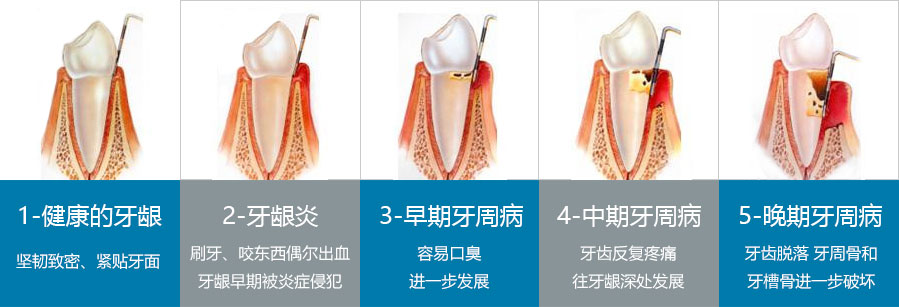

牙周炎怎么治疗

很多牙周炎患者的牙周炎发展到一定程度才引起重视。康贝佳提醒大家如果发展到重度牙周炎时,牙根分叉病变、牙髓病变、牙松动甚至脱落就会随之而来。因此,牙周炎重点应... [详情]

牙龈经常出血

很多人在刷牙时或吃饭后牙龈出血,有的在吃馒头、水果时在食物上留有血印,甚至睡醒后枕头上有从嘴里流出的血迹,这些现象都可能是牙龈出血。为什么牙龈会出血呢? 牙龈... [详情]